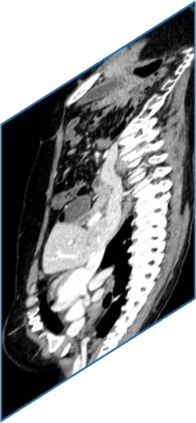

Due to the constraints of the imaging device and high cost in operation time, computer tomography (CT) scans are usually acquired with low intra-slice resolution. Improving the intra-slice resolution is beneficial to the disease diagnosis for both human experts and computer-aided systems. To this end, this paper builds a novel medical slice synthesis to increase the between-slice resolution. Considering that the ground-truth intermediate medical slices are always absent in clinical practice, we introduce the incremental cross-view mutual distillation strategy to accomplish this task in the self-supervised learning manner. Specifically, we model this problem from three different views: slice-wise interpolation from axial view and pixel-wise interpolation from coronal and sagittal views. Under this circumstance, the models learned from different views can distill valuable knowledge to guide the learning processes of each other. We can repeat this process to make the models synthesize intermediate slice data with increasing inter-slice resolution. To demonstrate the effectiveness of the proposed approach, we conduct comprehensive experiments on a large-scale CT dataset. Quantitative and qualitative comparison results show that our method outperforms state-of-the-art algorithms by clear margins.